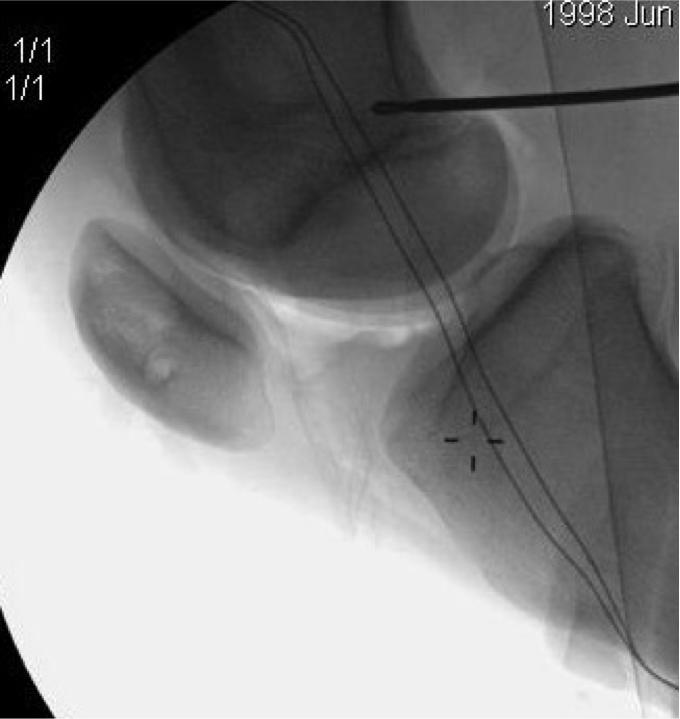

Xray 2

Finding Schottles Point